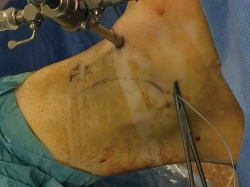

La pierna se coloca en una pernera que sujeta la tibia paralela al suelo y con una posición del tobillo en anteroposterior respecto al suelo, dejando el tobillo libre en el aire, lo que permite una gran zona de trabajo alrededor del mismo (Figura 1).

Una vez colocado en la posición anteriormente descrita, marcamos todas las estructuras anatómicas (maléolos, nervio peroneo superficial, tendón peroneus tertius/extensor del 5.º dedo y tendón tibial anterior) que nos permitirán realizar los portales minimizando el riesgo de lesionar estructuras neurovasculares y tendinosas(10)(Figura 2).

Figura 1. Colocación de la pierna en la pernera que permite un gran ángulo de trabajo.

Figura 2. Marcaje de la anatomía del aspecto anterior del tobillo, para protección de la misma y facilitar el trabajo.